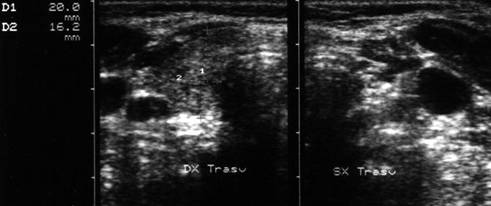

Lob drept, proiectie trasversala. Lob

stang, proiectie trasversala.

Lob drept, proiectie longitudinal. Lob stang, proiectie longitudinala.

Femeie de 41 ani. Tiroida de consistenta dura, foarte

dureroasa la palpare, cu suprafata neregulata.

Ecografia: moderata crestere a volumului; marginile lobilor rau definite; structura

intens ne mogena cu alternanta de arii hipoecogene, de edem si altele intens ecogene,

cu aspect pseudonodular.

Examene de laborator: moderat hipertiroidism; indici de fibroza foarte ridicati.